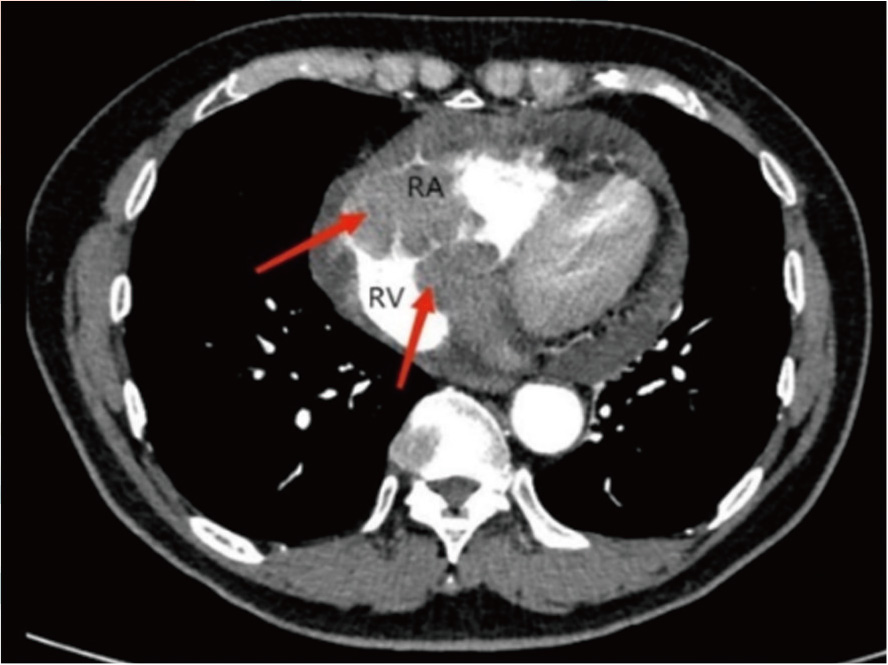

原发性心脏淋巴瘤(PCL)是极其罕见的一类心脏肿瘤,因其病情进展迅速、侵袭性强,症状、体征不明显,极易延误治疗。现报道1例应用3D打印技术辅助诊断和治疗PCL患者的诊疗经过,为临床PCL患者的诊疗提供参考。

任志鹏, 张根, 王欢, 戴自强, 何东升, 杜保罗, 李欣, 李巅远. 3D打印技术辅助诊断和治疗原发性心脏弥漫大B淋巴瘤1例[J]. 国际肿瘤学杂志, 2025, 52(4): 253-256.